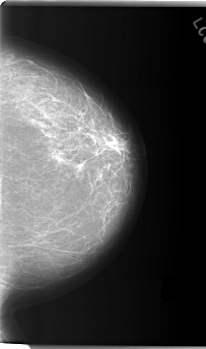

C_0169_1.RIGHT_MLO

LEFT_CC LINES 5928 PIXELS_PER_LINE 3488 BITS_PER_PIXEL 12 RESOLUTION 50 NON_OVERLAY